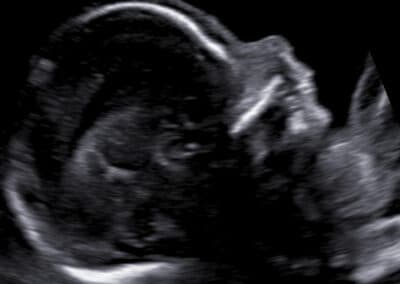

Chybějící nosní kůstka, která patří ke znakům Downova syndromu I dalších genetických vad

Určíme uložení a stav placenty, množství plodové vody a počet cév v pupečníku. Změříme velikost příčného průměru a obvodu hlavičky, obvod bříška a délku stehenní kosti miminka a určíme jeho hmotnost. Vyšetříme také podrobně všechny jeho orgány, hledáme přitom nejen orgánové vady, ale i malých odchylky normálního vzhledu, tzv. markery genetických vad. Pokud si budete přát znát pohlaví miminka, rádi vám jej sdělíme. Při vyšetření mozku miminka, případně lebky a dalších orgánů si pomáháme ke zpřesnění vyšetření i využitím 3D ultrazvuku. Budete-li si přát připojit 3D-4D ultrazvukové vyšetření s reálným zobrazením vzhledu obličeje vašeho miminka , rádi jej také připojíme.